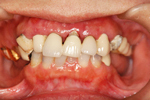

① 上の顎・治療前

② 前から見た状態・治療前